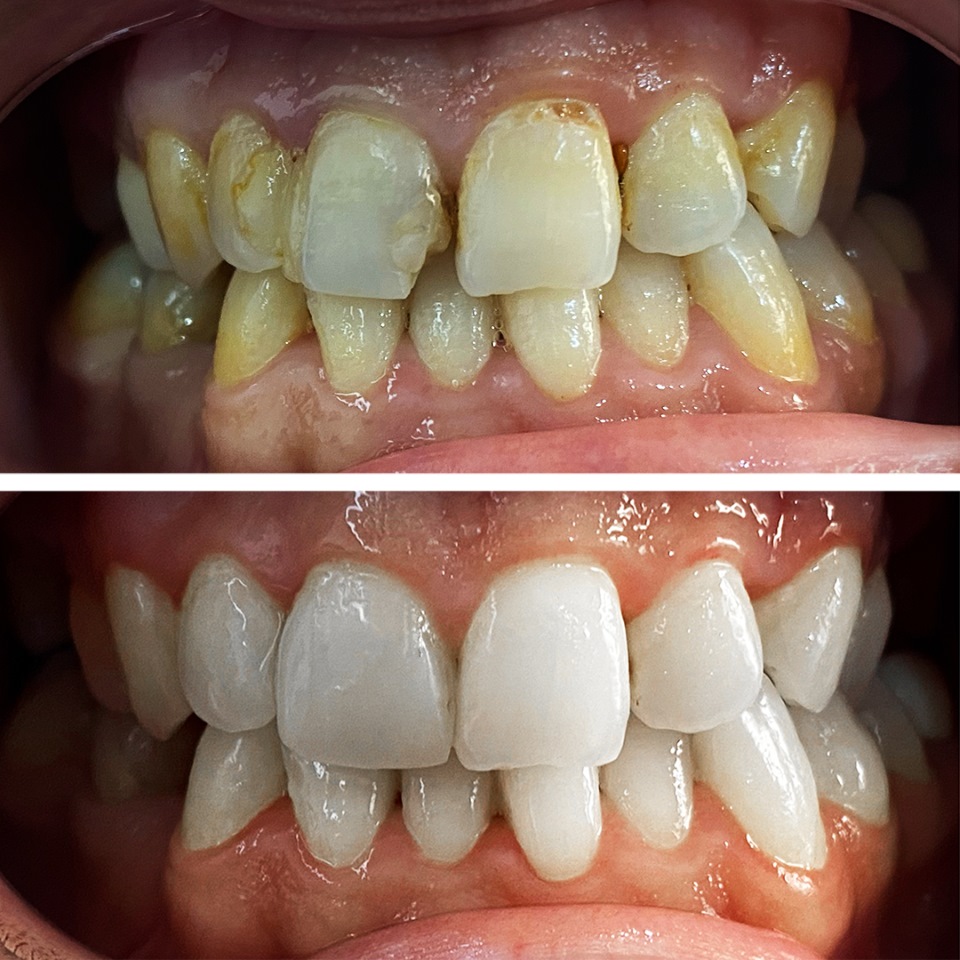

Smile Dental Clinic Turkey Gallery

Our Gallery and Happy Patients

Let’s make a change and put a perfect smile on your face with our dental clinic in Antalya/TURKEY.